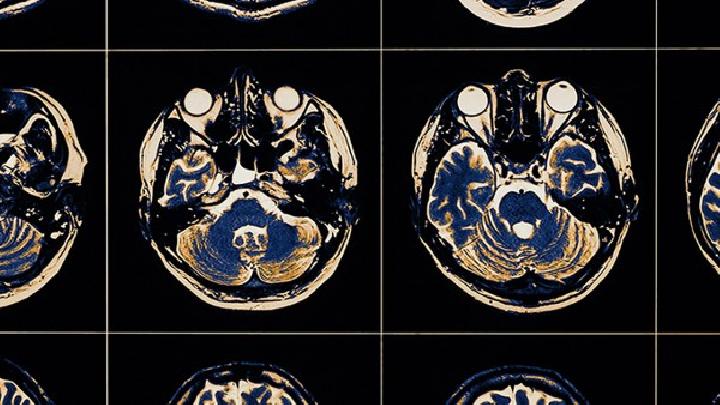

在我们的生活中,许多新生儿患有脑积水,由于脑积水,许多婴儿的身体受到严重伤害,所以许多父母对此感到非常痛苦。所以让我谈谈预防儿童脑积水的方法。

1.脑积水的早期产前诊断是预防脑积水出生的重要途径。由于明显的脑积水,可在怀孕12-18周内通过B所以要加强超查B应用于产前诊断,尽快终止妊娠,防止脑积水出生,降低先天性脑积水出生率。